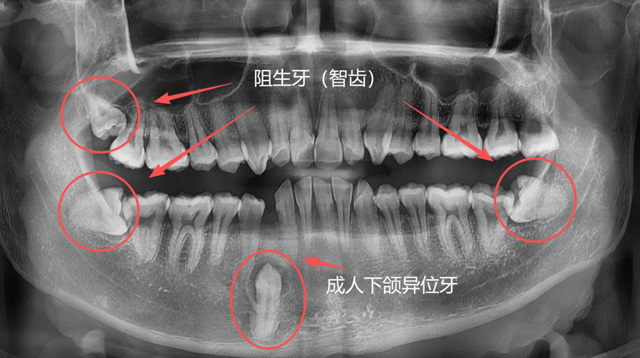

成人异位牙、阻生牙(智齿)

有些人因为牙列拥挤、乳牙滞留或先天发育等原因,恒牙没有在正常的位置萌出,反而往上颌窦、鼻腔等方向生长;称为“异位牙”,还有的牙因为全部或部分埋在了牙槽骨里,无法萌出,称为“阻生牙”,很多智齿就是这样的情况;还有一些超出正常数量的“多生牙”,通常也埋在牙槽骨里无法萌出。

刘伟博士:解剖位置、解剖结构异常的牙齿,拔牙难度更大一些。包括位置异常的阻生牙、异位牙,结构异常的如牙根弯曲、牙根多的牙,还有因为长期慢性炎症造成牙周粘连的牙,以及一些完全退缩到骨头里面的残根,都有一定的难度。

问:什么样的牙比较难拔?

医生怎么能知道这颗牙的情况呢?只用肉眼看是不够的,我们要通过口腔全景片、CBCT这些影像学检查资料来了解牙齿的解剖位置,了解牙根的数量和形态,以及有无根尖囊肿和炎症。

一般来说,前牙和前磨牙单根的比较多,磨牙一般是两个根以上,智齿也就是第三磨牙,牙根数目变异情况比较大,一般有两个根,也有一个根(融合根)、三个根或四个根的,对于靠近神经和血管的牙,或长在上颌窦等异常位置的牙,我们的手术操作会更加复杂一些。

长在上颌窦、鼻腔方向的异位牙,长在牙槽骨深处的多生牙,常常埋伏于骨内,需要骨开窗才能拔除,具有一定的难度。